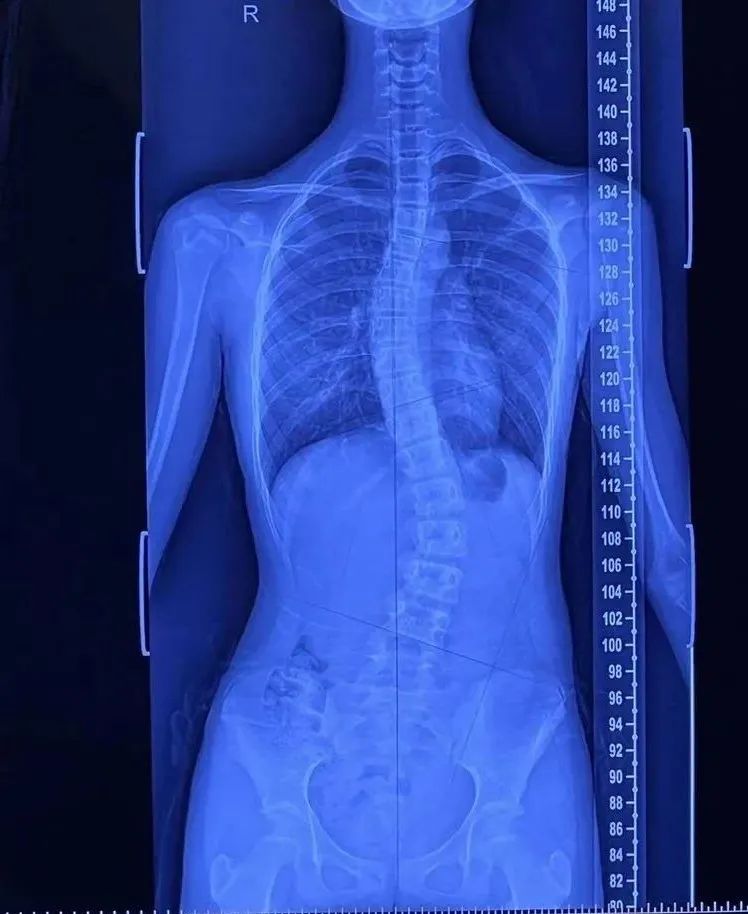

青少年特发性脊柱侧弯(AIS)是一种复杂的三维脊椎畸形,其发病机制尚不明确,成为继肥胖症、近视之后我国青少年儿童的第三大“杀手”。我国青少年该病的发病率约为2.4%,并且随年龄的增长呈上升趋势,男女比例约为1:1.52早期症状并不明显,青少年骨骼生长较快,若治疗不及时,侧弯畸形迅速加重,造成腰背部慢性疼痛、心肺功能下降、心理疾病、日常生活能力下降等。

脊柱侧弯的表现

1.外形改变:剃刀背、高低肩、长短腿、身体扭曲等。

Cobb角<10°,只需要定期观察,不需要特殊处理;

10°~20°时建议选择运动治疗干预;

20°~45°时选择支具治疗联合运动治疗;

>45°时考虑手术治疗。